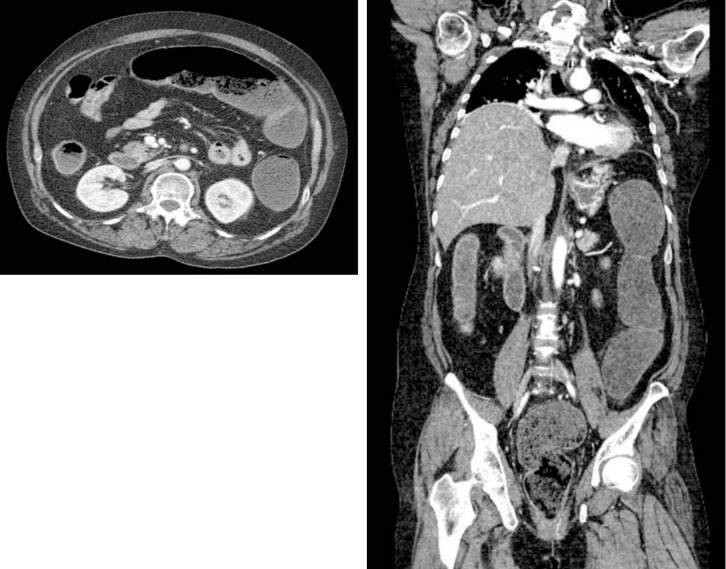

高镁血症是一种罕见但有潜在致命危险的电解质紊乱,因其陌生而经常被忽视。镁通过骨骼、肠道吸收和肾脏排泄的平衡进行调节。高镁血症通常是由于镁摄入过多或肾脏排泄减少引起的,但肾功能正常的患者也会出现高镁血症。在此,我们报告了两例服用氢氧化镁治疗便秘的高镁血症患者。第一个病例涉及一名患有终末期肾病的 82 岁妇女,她在每天服用 3000 毫克氢氧化镁治疗便秘后,因高镁血症引发了代谢性脑病。她的血镁水平为 9.9 毫克/分升。她的治疗包括停用氢氧化镁和继续进行血液透析,最终她康复了。在第二个病例中,一名有脑出血和智力迟钝病史的 50 岁女性出现了高镁血症,尽管她的肾功能正常。她还在服用氢氧化镁治疗便秘,镁含量为 11.0 毫克/分升。在准备接受持续肾脏替代疗法(CRRT)时,她的心脏骤停。自主循环恢复后,CRRT 启动,她的血镁水平呈下降趋势。然而,生命体征和乳酸水平并未恢复,最终导致死亡。这些病例强调了及时诊断和干预高镁血症的重要性,以及定期监测接受含镁制剂治疗的患者(尤其是肾功能受损的患者)体内镁水平的必要性。

Hypermagnesemia is a rare but potentially fatal electrolyte disorder often overlooked because of its unfamiliarity. Magnesium is regulated through a balance of bone, intestinal absorption, and renal excretion. Hypermagnesemia typically arises from excessive magnesium intake or reduced renal excretion; however, it also occurs in patients with normal kidney function. Herein, we report two cases of hypermagnesemia in patients taking magnesium hydroxide for constipation. The first case involved an 82-year-old woman with end-stage renal disease who developed metabolic encephalopathy due to hypermagnesemia, after taking 3,000 mg of magnesium hydroxide daily for constipation. Her magnesium level was 9.9 mg/dL. Her treatment involved discontinuing magnesium hydroxide and continuing hemodialysis, which led to her recovery. In the second case, a 50-year-old woman with a history of cerebral hemorrhage and mental retardation developed hypermagnesemia despite having normal renal function. She was also taking magnesium hydroxide for constipation, and her magnesium level was 11.0 mg/dL. She experienced cardiac arrest while preparing for continuous renal replacement therapy (CRRT). After achieving return of spontaneous circulation, CRRT was initiated, and her magnesium level showed a decreasing trend. However, vital signs and lactate levels did not recover, leading to death. These cases highlight the importance of prompt diagnosis and intervention for hypermagnesemia and the need to regularly monitor magnesium levels in individuals receiving magnesium-containing preparations, especially those with impaired kidney function.